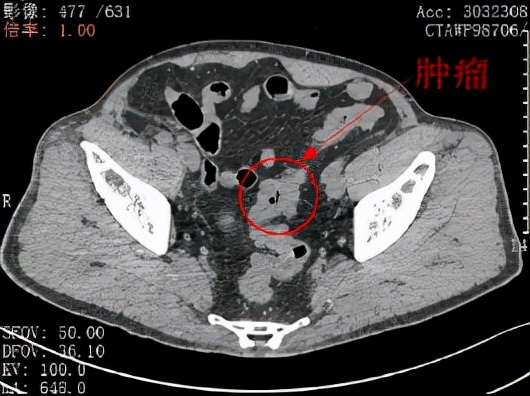

程先生(化名)2021年9月经确诊为乙状结肠癌。图为CT影像图中看到的肿瘤(红色圈部分)。

了解了程先生的顾虑之后,北大深圳医院胃肠外科主任吕国庆主任医师率团队对程先生的病情进行了评估:其肿瘤位于乙状结肠,肿瘤分期属于中期,大小约3厘米×2厘米,距肛门35厘米。在评估了患者移植肾的功能及术后可能发生的肾损伤概率之后,经过仔细讨论,医生团队认为可以为患者实行腹腔镜微创NOSES手术。